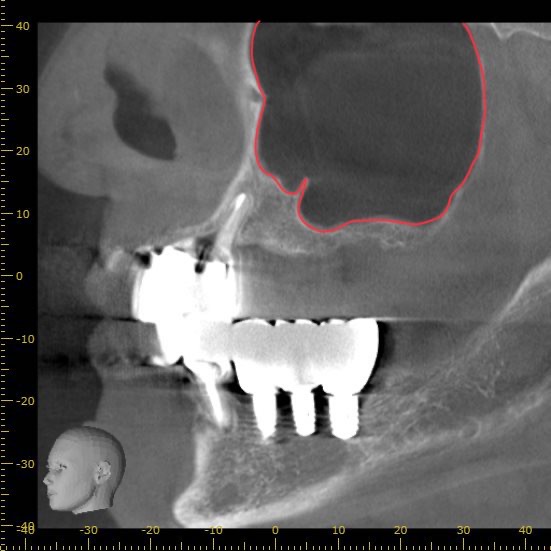

横から見たCT画像です。

上顎の上方には副鼻腔(上顎洞)と呼ばれる、鼻とつながる空洞が存在します。

下の赤線で囲まれた部分です。

この部分にインプラントが飛び出してしまうと鼻に炎症を起こす可能性があるため、その下の骨の内部で留める必要があります。

今回の画像をみるとわかりますが、骨が極端に少ない状態です。